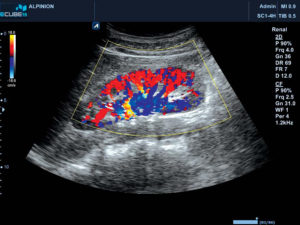

Цветовое разрешение показателей, иначе цветовое допплеровское картирование (ЦДК) имеет большую информативность, поскольку, фактически, исключает ошибки при диагностике. Красным цветом на мониторе отображается кровоток, направленный к датчику, голубым – движение кровотока от датчика. Яркость цвета определяется скоростью процесса тока крови.

ЦДК, как вид УЗИ, основанный на Допплеровском эффекте, позволяет оценить сосудистый кровоток. Основой ЦДК является сочетание черно-белого изображения в УЗИ-диапазоне и оценки тока крови по допплеру.

Когда аппарат установлен в режим ЦДК, врач может видеть на мониторе обычное УЗ-изображение. В той его части, которая изучается, в цвете даны скорости потока крови.

Способы цветной кодировки картограммы следующие:

- оттенками красного цвета кодируют скорость кровотока, движущегося по направлению к датчику;

- оттенками голубого – скорость тока крови, движущейся от датчика.

Цветное допплеровское картирование дает врачу возможность максимально точно рассмотреть характеристики кровотока в почечных сосудах, с использованием цвета

Чем менее насыщенный цвет, тем, соответственно, меньше скорость. Кроме того, на мониторе отображена оттеночная шкала и ее расшифровка (описание соответствия оттенка-скорости).

ЦДК визуально отображает и анализирует: направление, скорость и характер потока крови, проходимость, сопротивление и диаметр изучаемого сосуда.

Приведем некоторые нормальные показатели почечных артерий:

Диаметр:

- основной ствол — 4,5±1,2 мм.;

- сегментарные артерии — 2,1 ±0,2 мм.;

- междолевые артерии — 1,5±0,1 мм.;

- дуговые артерии — 1,0±0,1 мм.

Систолическая (1) и диастолическая (2) скорость кровотока:

- основной ствол — 73±26 и 37±1 см/сек.;

- сегментарные артерии — 45±8 и 22±4 см/сек.;

- междолевые артерии — 32±3 и 13±4 см/сек.;

- дуговые артерии — 23±3 и 10±2 см/сек.